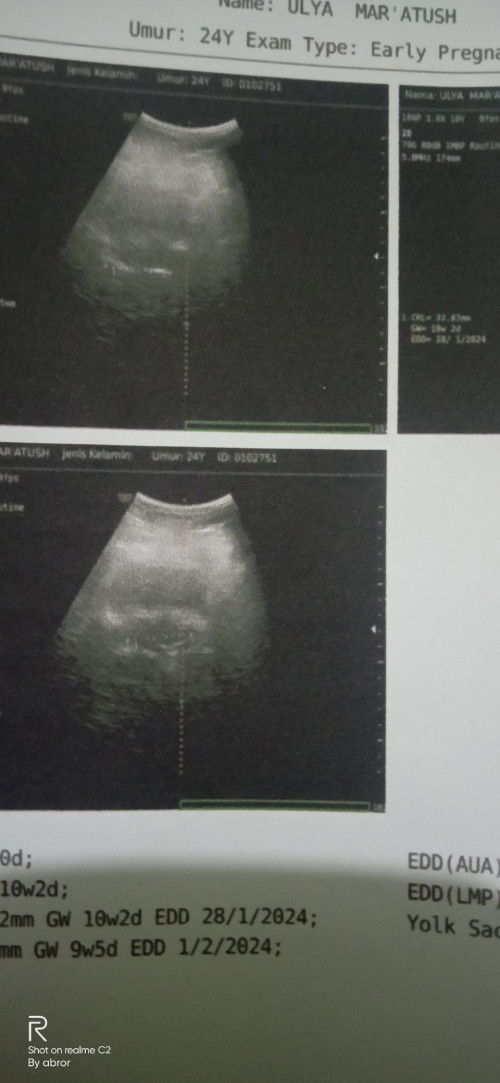

#bantusharing bunda. Aq usg 2d tp hasilnya seperti ini,ada yg tau nggk ini janinnya yg mana Apa karna alatnya pernah rusak jdnya gambarnya kurang jelas